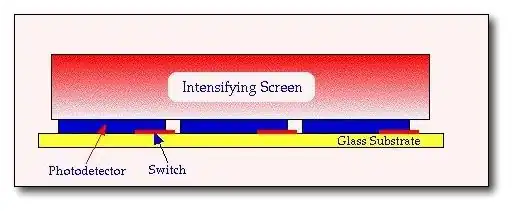

- Indirect Image Receptors

- Indirect receptors are based on coupling an fluorescent screen to the active matrix array. Phosphors such as Gd2O2S:Tb and CsI:Tl have been used, and the light produced following X-ray interaction is detected by an array of pixels consisting of photodetectors – see the following figure:

- Each photodetector generates an electric charge that is proportional to the amount of light striking it, and this charge is stored until it is read-out by the switching control circuitry. The detection process is referred to as indirect since the detected X-rays are first converted to light, which is subsequently converted to electric charge.